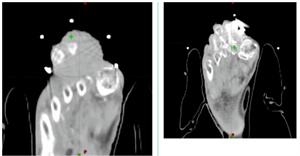

新开展电子耳蜗植入术、骨科机器人手术、肌骨超声引导下介入治疗技术等新技术10项;开展赣西地区首台骨科机器人辅助下行髋关节、膝关节置换术,省内率先开展飞秒激光辅助白内障角膜散光激光松解术,省内地市级医院率先开展非体外循环介入主动脉瓣膜置入术,萍乡市首例支气管镜下PTS注射治疗,萍乡本地率先开展经皮穿刺肺部肿瘤热消融术、反式人工肩关节置换手术、房颤冷冻消融术等高难度诊疗技术项目,多项技术填补萍乡地区空白。